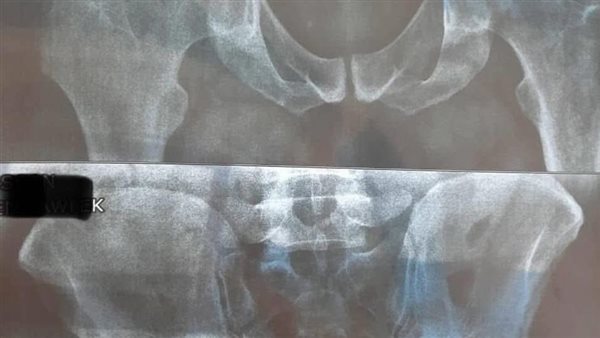

نجح فريق طبي بمستشفى الخانكة التخصصي بمحافظة القليوبية، في إجراء 30 عملية تغيير مفصل صناعي.

من جانبه، أكد الدكتور سيد سليمان مدير مستشفى الخانكة التخصصي، أن العمليات جرت على أيدي أمهر الاستشاريين والجراحين، وفي غرف عمليات مجهزة وخدمة إقامة فندقية مميزة، لافتا إلى أن النجاح ليس مجرد كلمة بل نتيجة خبرة ودقة ورعاية طبية على أعلى مستوى.

وأوضح مدير المستشفى، أن الخدمة متاحة من خلال نظام اقتصاد، ونفقة الدولة والتأمين الصحي، وشركات متعاقدة، والأطباء من خارج المستشفى (ضمن منظومة العمليات الفندقي).